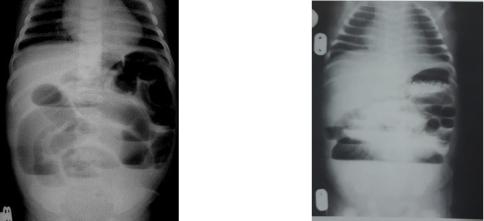

Рентгенологическое исследование брюшной полости – обзорная рентгенограмма брюшной полости в вертикальном положении. При низкой кишечной непроходимости на обзорных рентгенограммах можно выявить повышенное газонаполнение петель кишечника, дилятированные петли, иногда наличие уровней.

Ирригография (исследование проводится с водорастворимым контрастным веществом, введенным через прямую кишку), при этом:

в случае непроходимости контрастируется резко суженная толстая кишка;

очень высокое стояние слепой кишки — при синдроме Ледда;

очень низкое стояние слепой кишки — при острой форме болезни Гиршпрунга;